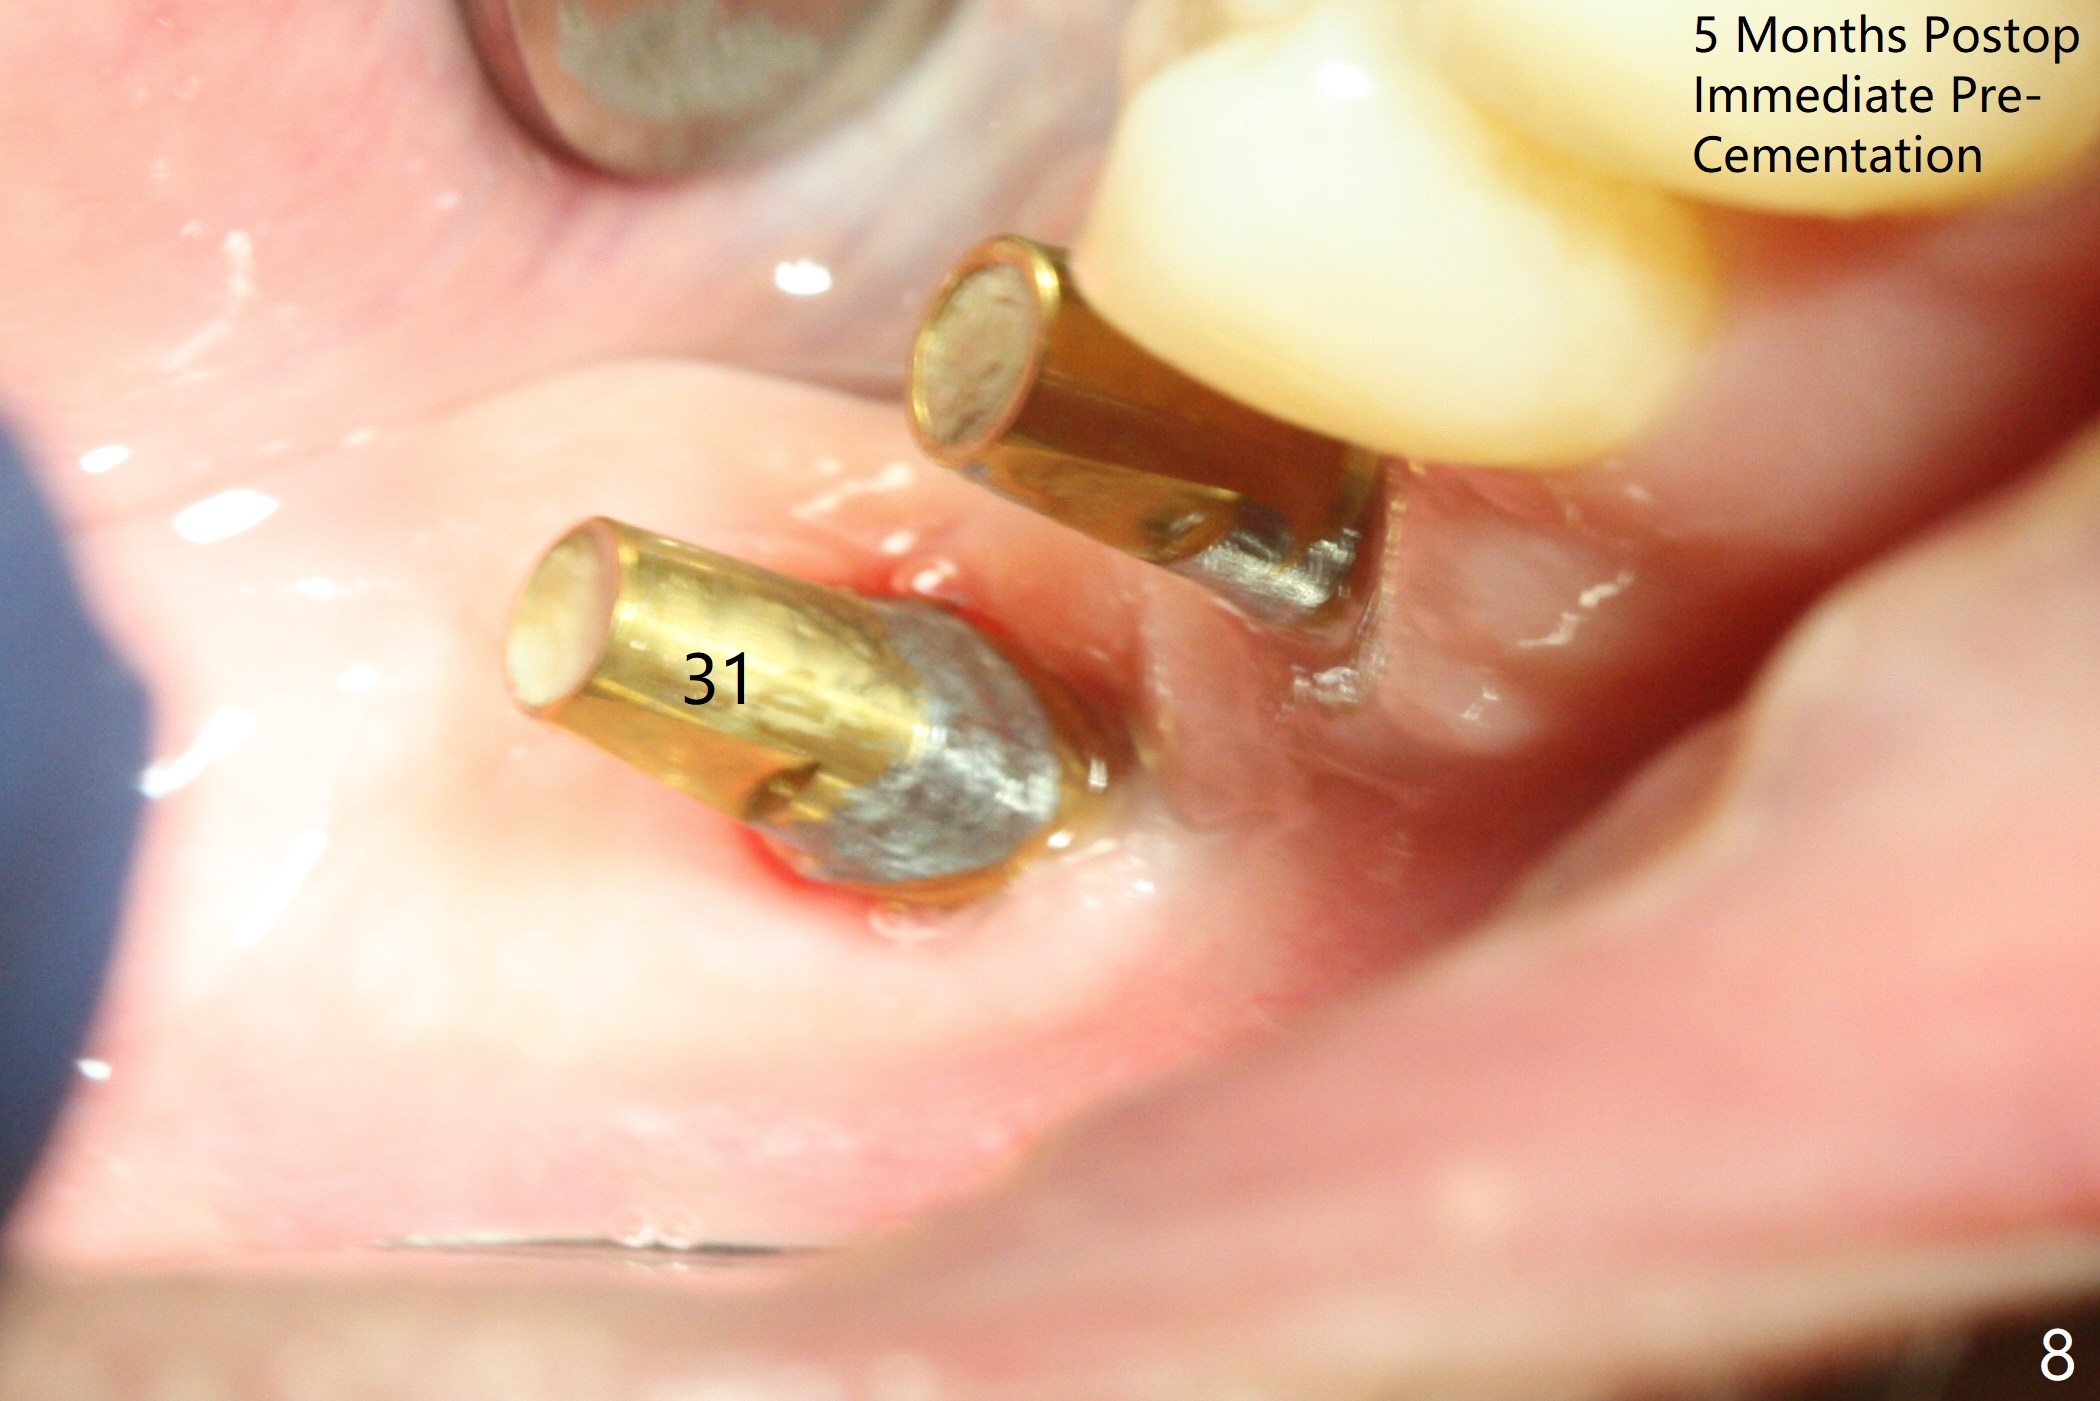

Osteotomy at the sites of #30 and 31 is initiated with Magic Split, followed by Magic Expanders (3.0 and 3.8 mm) at #31. Initial depth of osteotomy is 13 mm with 2.2 mm drill (Fig.1). After adjustment of the trajectory at #31 (Fig.1 arrow) and deepening the osteotomy by 2 mm, dummy implants are placed with stability (Fig.2). Following increase in osteotomy at #31, the larger implant in fact loses stability (Fig.3). The loose implant is pushed distal (Fig.4 arrow) with placement of autogenous bone mesial (*). The stable implant at #30 (Fig.3) and its abutment (Fig.4) are used as a post to hold periodontal dressing, which covers the wound at #31 after placement of collagen plug and suturing. In fact the same technique could be used when socket preservation was performed if an implant were placed at #30 at the same time. When the periodontal dressing dislodges, the wound at #31 heals uneventfully (Fig.5,6). The bone graft seems to remain in place 3 months postop (Fig.7). The implant is uncovered with placement of a 6.8x7 mm healing abutment 4 months postop. When a cementation abutment is placed and prepped, the buccal margin is much lower than the lingual (Fig.8 taken prior to cementation). The patient enjoys mastication with the new implant crowns 3.5 months post cementation (Fig.9).